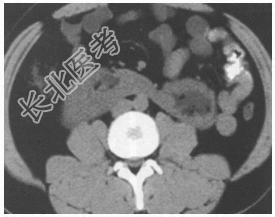

- [材料题] 患者男性,31岁,主因"发现左肾积水3个月"就诊。无腰痛,无发热,无尿频、尿急,无呕心呕吐。门诊行B超检查:提示左肾轻度积水,双肾下极融合。入院后行腹部CT平扫及三维重建(见图)。

- 简答题1、该患者的正确诊断是

- 简答题2、该疾病的影像学特征包括